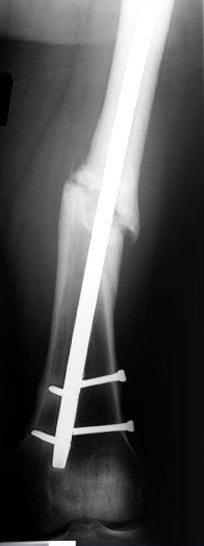

Из трех вариантов:

Рассверливание с заменой более большого диаметра штифтом,

Остеотомия с фиксацией пластиной+костная пластика,

Аппарат Илизарова= Taylor spatial frame

Гвоздь для ротационных смещениц был бы идеальнымимплантом, после коррекции есть возможность блокировать, но из-за укорочения метод оставил на последнее место. Есть метод Сhaplan лечения ложных суставов бедра, где необходимость bone graft, накладывается феморальный дистрактор и после удаления штифта - рассверливание, через проксимальный канал вводят костный графт в место ложного сустава под рентген контролем, потом вводят штифт, кстати, само рассверливание дейстивует как стимулятор - активизирует восстановительный процесс.

Обычный мой первый выбор - вариант с пластиной, - учитывая бывшую инфекцию, открытую травму, посчитал метод менее приемливым.

Еще больной был противв костной аутопластики, да и самому тоже хотелось перейти к истокам "откуда мы" более усовершенствованному Курганскому методу.

Операцию провели в два этапа, сперва удалили штифт, рассверливание римером на пару мм большего диаметра, определение чувствительности на анаэробную и аэробную культуру (где исследования показали негативный результат чувствительности), через дней десять - начали аппаратную фиксацию.